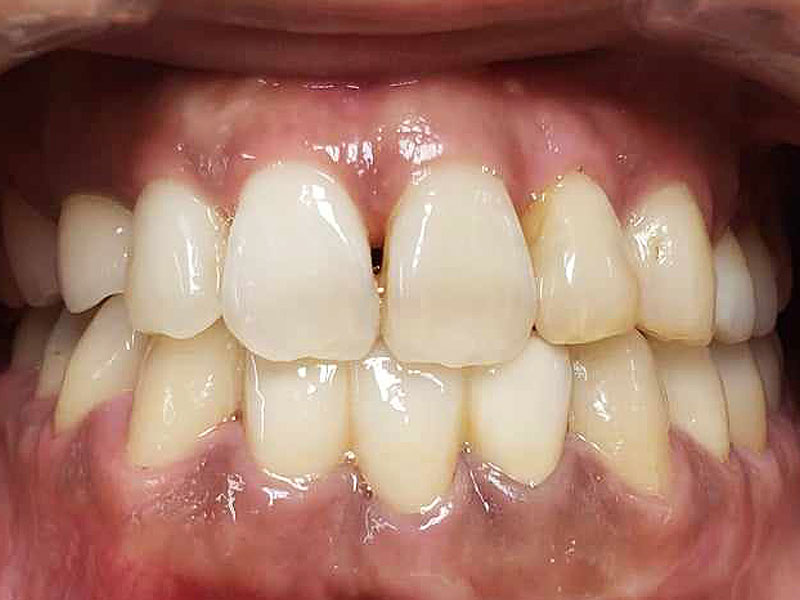

術後

トータルの治療期間は3年くらいでしたが、包括歯科治療(虫歯治療、歯周病治療、抜歯、矯正治療、歯内治療、修復治療、メンテナンス)を1人の歯科医が行い、まずまずの治療を行うことができたのではないかと思います。患者さんも十分に満足されました。

ただ、後年(2年後)、下前歯はブラックトライアングルの改善ならびに保定も兼ねて、3本前歯は連結修復を行いました。4か月メンテナンスに移行です。

術後10年後

メンテナンスのみで、今のところ再治療を行った歯はありません。うまくコントロールされていると思います。ただ、鼻性由来の両側副鼻腔炎を患ってたので、耳鼻科への来院を促しました。